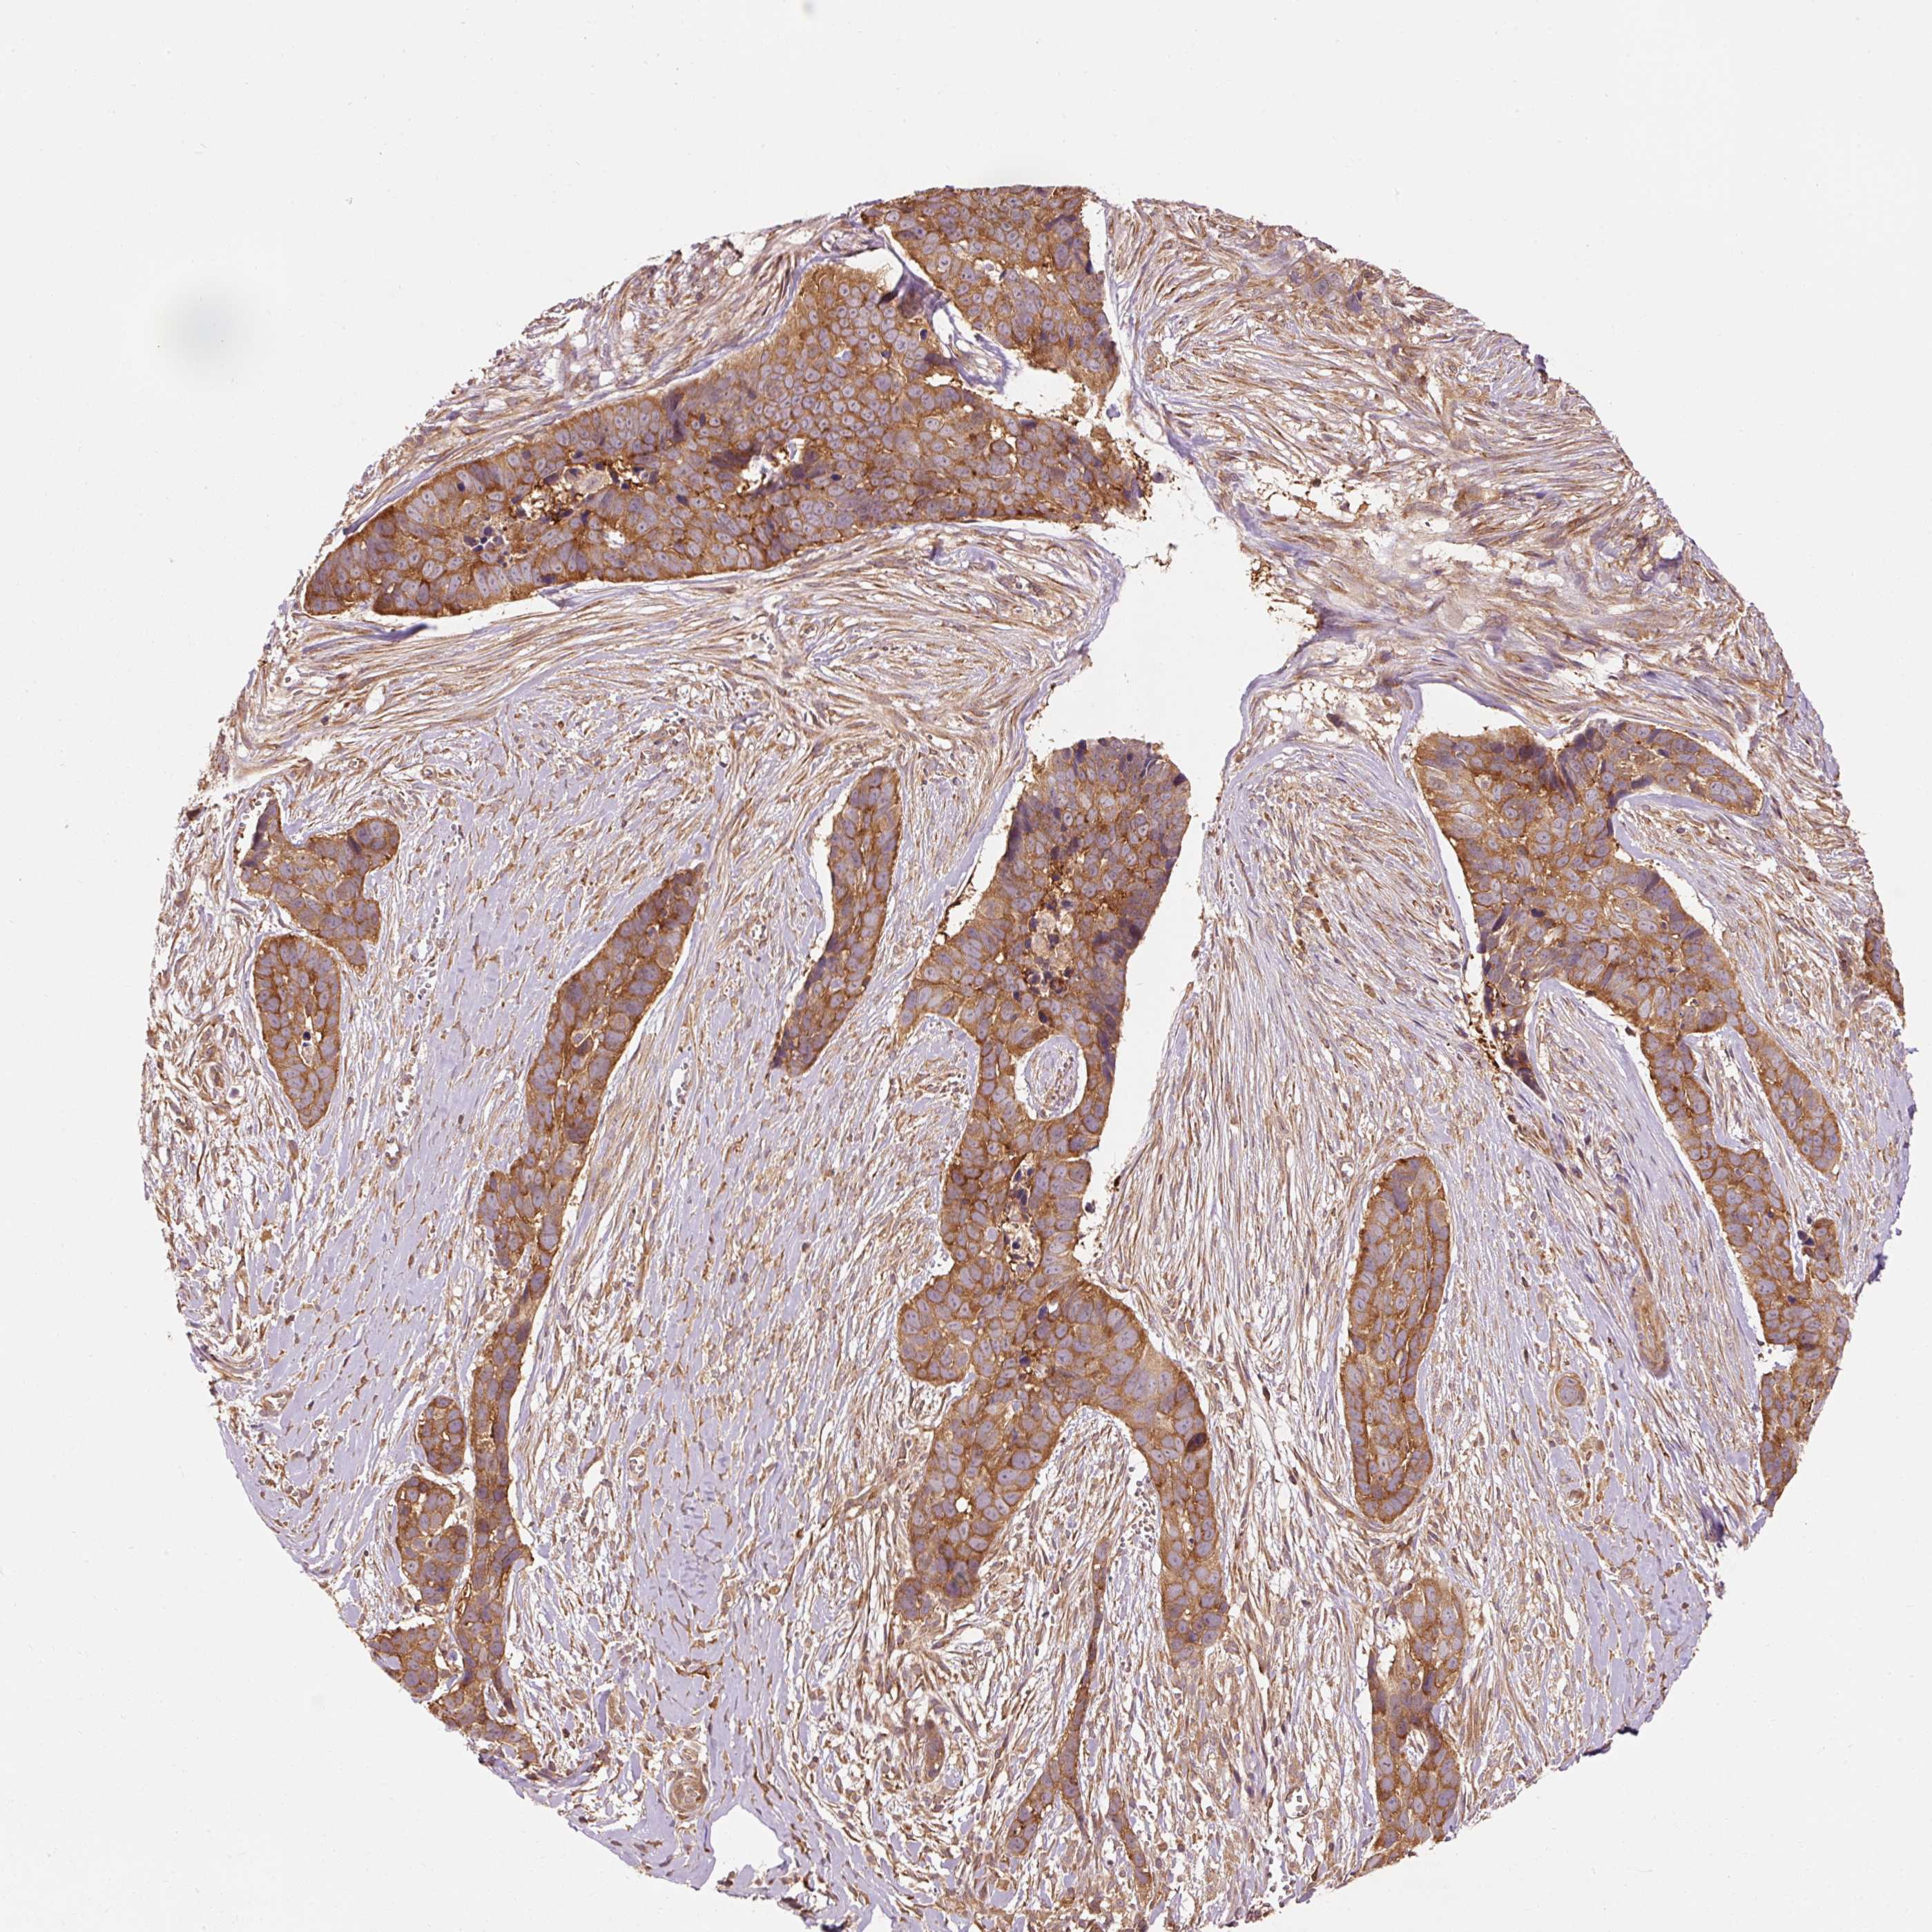

SKIN CANCER - Protein expressioni

A mouse-over function shows sample information and annotation data. Click on an image to view it in a full screen mode. Samples can be filtered based on level of antibody staining by selecting one or several of the following categories: high, medium, low and not detected. The assay and annotation is described here.

Antibody stainingi

Antibody staining in the annotated cell types in the current human tissue is reported as not detected, low, medium, or high, based on conventional immunohistochemistry profiling in selected tissues. This score is based on the combination of the staining intensity and fraction of stained cells.

Each image is clickable and will lead to virtual microscopy that enables deeper exploration of all samples and also displays staining intensity scores, fraction scores and subcellular localization as well as patient and tissue information for each sample.

Staining

High

Medium

Low

Not detected

Intensity

Strong

Moderate

Weak

Negative

Quantity

>75%

75%-25%

<25%

None

Location

Nuclear

Cytoplasmic/membranous

Cytoplasmic/membranous,nuclear

Basal cell carcinoma

Squamous cell carcinoma, NOS